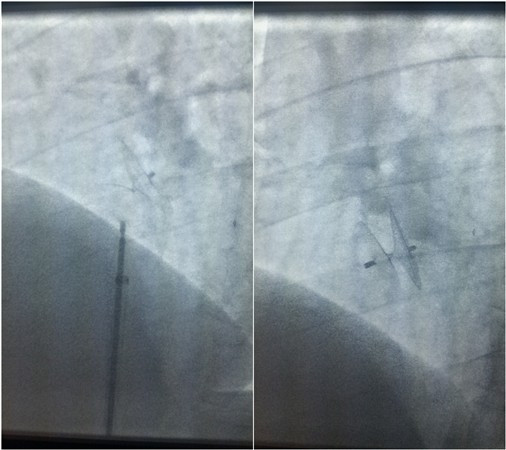

手术进行中

神经内科张茹教授、心血管外科裴斐教授、超声科刘保民教授针对上述病例进行会诊讨论,认为依据国内外目前共识,患者不明原因的头痛、头晕症状以及反复发作的脑卒中可能与PFO所致反常栓塞相关,可试行PFO封堵术。经充分沟通,苦苦求医的2名患者及其家属重燃希望,积极要求行手术治疗。经术前充分准备,心血管外科相里伟、万俊哲、张伟团队在裴斐教授带领下与超声科刘保民教授合作,先后于2015年12月21日及12月31日进行了两例PFO封堵术,手术过程顺利。术后复查心脏彩超及右心声学造影,结果提示“房水平静息与负荷状态下均未见右向左分流”。2例手术患者术后恢复良好,前者无头痛、头晕发作,后者无新发脑卒中,均已顺利出院,定期随访。